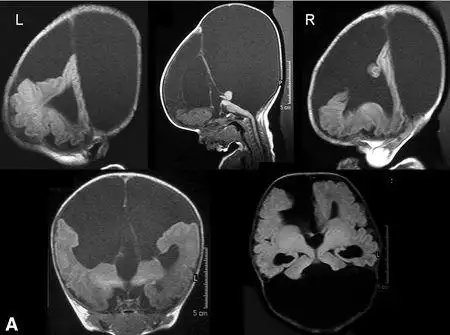

实战——叶状全前脑和中线变异型全前脑鉴别_case